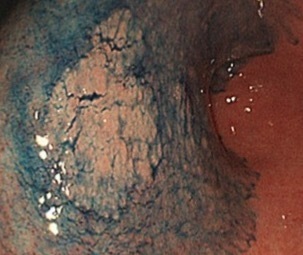

先ほどまでわかりにくかった早期胃がんこのような見つけにくい胃がんも

最高水準の診断技術で早期に発見できる

桐山クリニックでは、すべての胃カメラ検査で最新のハイビジョンモニターを使用し、内視鏡検査に特化された環境で検査を行っています。

粘膜を内視鏡で観察するときには、その粘膜の色の違いや粘膜表層の細かな小血管の密度、その血管の太まりなどの変化に注意しながら病変を見つけ、さらに診断していきます。

最高画質下で観察することで、病変が腫瘍であるのか、悪性のがんであるのかどうか、手術が必要か、それとも内視鏡で切除できるのか、適切な判断をする上で非常に有用です。